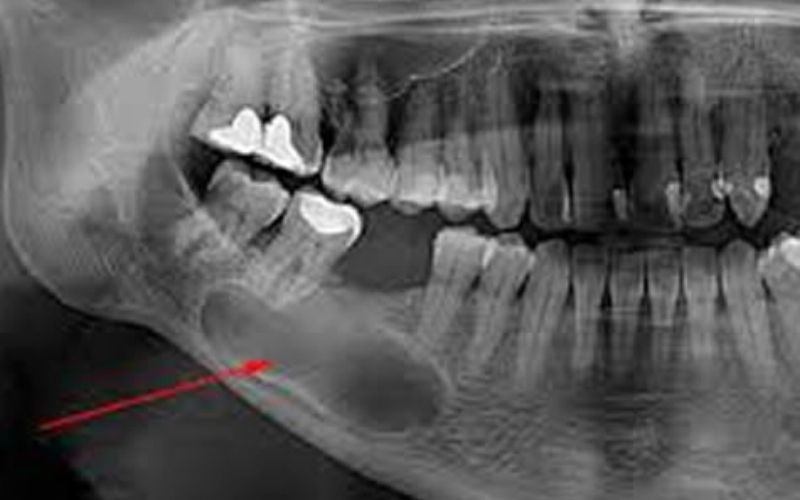

Kistler

Kistler ve Tümörler

Kistler genellikle iyi huyludur, cerrahiyle çıkarılır; tümörlerde erken teşhis önemlidir, tedavi cerrahi ve onarıcıdır.